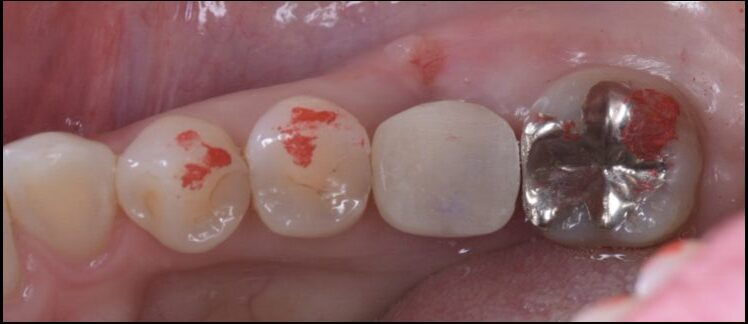

After

仮歯のSET後

仮歯の状態で8週間過ごしてもらいます。その後型取りを行いセラミックをSETしていきます。

セラミックSET後。